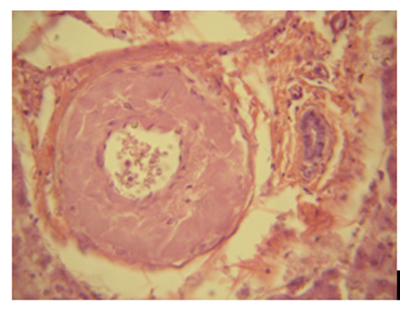

Ստամոքսի, տասներկումատնյա աղու, հաստ աղու բիոպտատների և սեկցիոն նյութի ուսումնասիրությունը և համեմատական վերլուծությունը պարզեց, որ ամիլոիդոզն առավել արտահայտված է հատկապես բարակ աղիների լորձաթաղանթի և ենթալորձային շերտի մանր անոթներում` մասնավորապես զարկերակիկներում, գեղձերի հիմային թաղանթներում (նկ. 1): Ամիլոիդային կուտակումներն այստեղ հաճախ նուրբ դեպոզիտների, իսկ երբեմն էլ առատ կուտակումների ձևով են հայտնաբերվել` տեղակայվելով նաև անոթների ադվենտիցիայում և շուրջադվենտիցիալ հյուսվածքում: Վերջինս վկայում է ՊՀ պայմանավորված ամիլոիդոզի ոչ միայն պերիռետիկուլյար, այլև պերիկոլագենային բնույթի մասին:

| Նկ.1. Ամիլոիդային դեպոզիտներ բարակ աղիների ենթալորձային շերտի անոթների պատերում, կոնգո կարմիր, x400 |